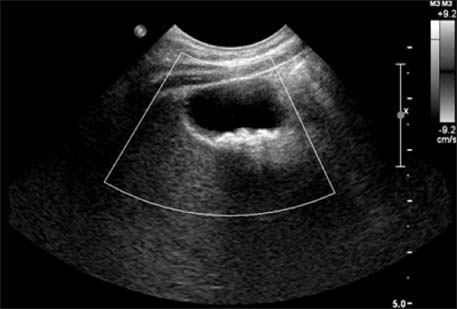

Fig. 1

CT shows multiple gallbladder stones (case 1).